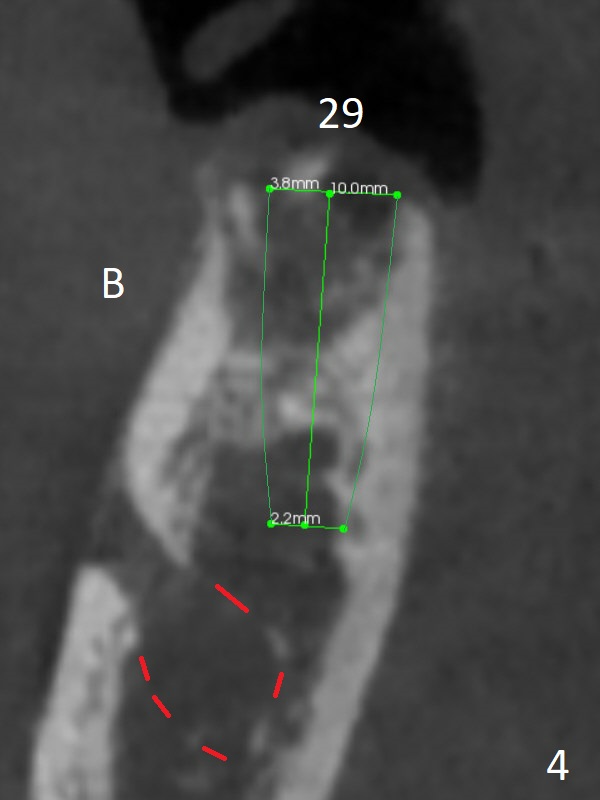

A 79-year-old woman with osteoporosis has a lower RPD, which becomes loose when #29 was extracted a few months earlier. The tooth #22 has mobility II (Fig.2 (increased pdl)), while the tooth #27 is short with periapical radiolucency (Fig.1,3 ^). The latter needs RCT and crown. For #29 implant placement, osteotomy should be underprep: 2 mm drill for 12 mm for 10 mm long implant (2 mm gingiva), 2.7 mm for 8 mm (Fig.3,4 (low bone density)).